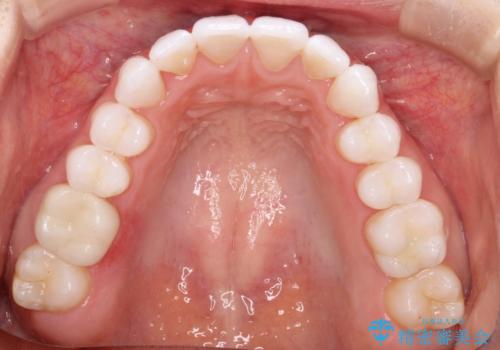

気になる前歯の歯並びをインビザラインで矯正

- 前歯の傾きと、ガタガタが気になるとのことで来院されました。

前歯の傾きや高さをシミュレーションで患者様と確認しながら、歯並びを仕上げていきました。